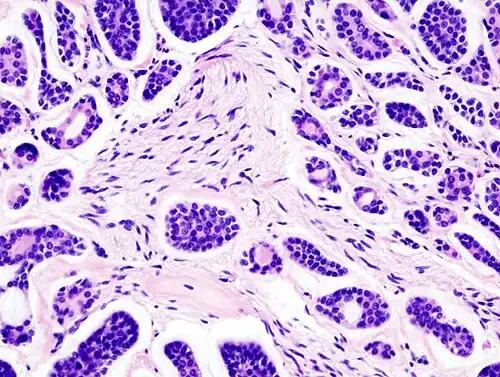

![]() | |

| Micrograph of an adenoid cystic carcinoma of a salivary gland (right of image): Normal serous glands, typical of the parotid gland, are also seen (left of image), H&E stain. | |

Histopathological image of adenoid cystic carcinoma of the salivary gland infiltrating a nerve (center), H&E stain -